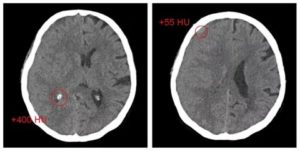

КТ является золотым стандартом для выявления геморрагии в первые 24 часа. Геморрагии также выявляются на МРТ. На КТ возможно определить 60% инфарктов в первые 3-6 часов, остальную часть возможно выявить впервые 24 часа. Общая чувствительность КТ при диагностике инфаркта составляет 64% и специфичность 85%. Ниже представлены ранние признаки на КТ.

Увеличение содержания воды в мозге на 1% приводит к снижению плотности головного мозга на КТ на 2,5 единицы Хаусфильда.

Обнаружение в первые 6 часов гиподенсной зоны является специфичным признаком необратимого ишемического повреждения мозга.

У пациентов с клиникой инсульта и выявленным гиподенсной областью впервые 6 часов есть риск увеличения зона ишемии, ухудшения симптоматики и кровотечения, а также данная группа пациентов имеет более хуже ответ на проводимую медикаментозную терапию в сравнении с пациентами с клиникой инсульта, у которых данная область не выявлена.

Таким образом выявления гиподенсной зоны является неблагоприятным прогнозом. Соответственно, что если гиподенсная зона не выявлена, это благоприятный прогноз.